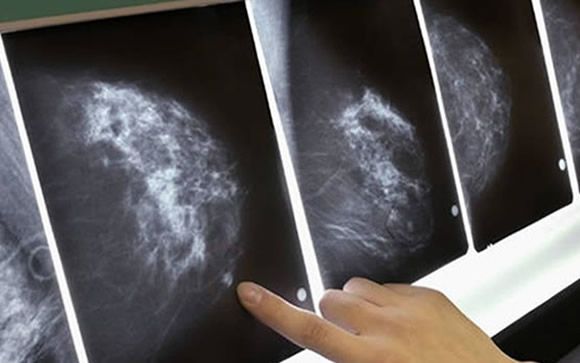

La incidencia del cáncer de mama está aumentando pogresivamente por el envejecimiento de la población

La guía plantea tres objetivos del seguimiento de las mujeres largas supervivientes de cáncer de mama: el diagnóstico de las recaídas o de un segundo tumor de mama, el minimizar el impacto de las secuelas y complicaciones derivadas del diagnóstico y tratamiento del cáncer de mama, y, por último, fomentar medidas de educación sanitaria y prevención con el fin de promover el bienestar y reducir los riesgos para la salud. Todo ello, con el fin de conseguir la mejor calidad de vida y lograr que las mujeres se puedan reincorporar a los distintos ámbitos de la vida social, familiar y laboral. “Desde hace varios años se ha manifestado la necesidad del seguimiento compartido entre ambas especialidades para garantizar una coordinación efectiva”, manifiesta Barnadas. “El médico de Atención Primaria tiene un papel destacado en la detección de recidivas y de segundas neoplastias, en el abordaje de los efectos tardíos del tratamiento oncológico, en la atención a la comorbilidad, en la atención psicológica, y en promover estilos de vida y recomendar estrategias de prevención de la salud, y en la medida de lo posible, de normalizar la atención sanitaria de las pacientes curadas de un cáncer de mama”.